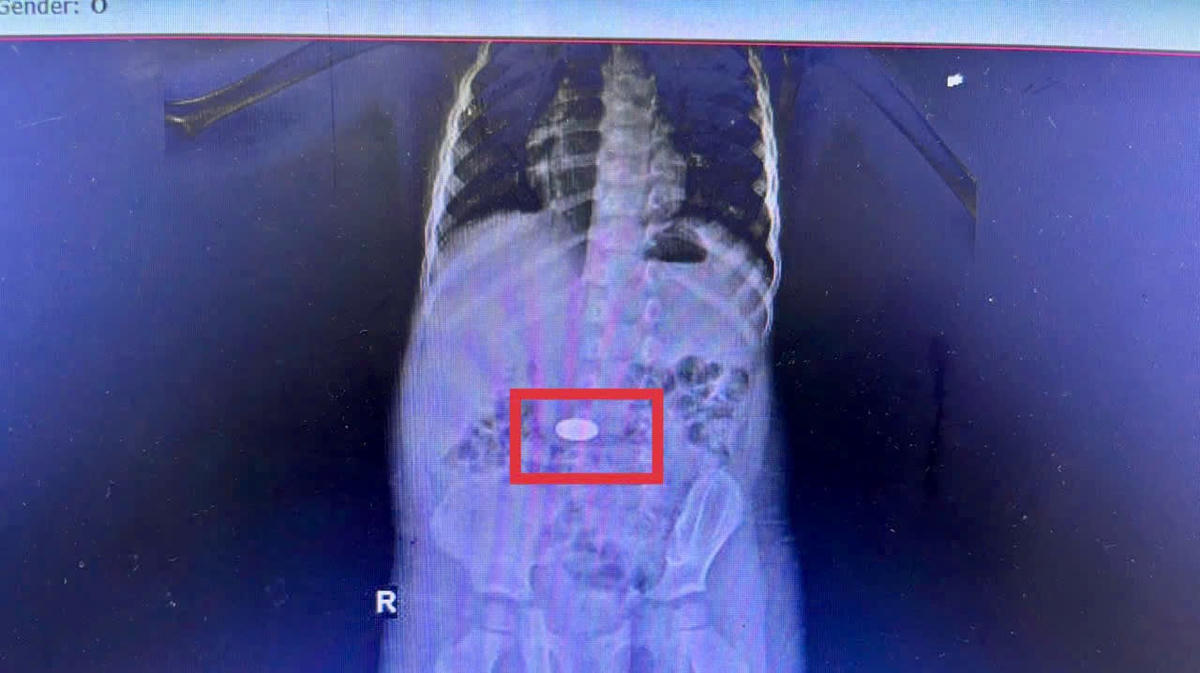

Kết quả chụp CT phát hiện dị vật nằm trong dạ dày của em bé 3 tuổi ở xã Khánh Vĩnh, tỉnh Khánh Hòa. Ảnh: BVCC

Cùng thời điểm trên, Bệnh viện Đa khoa tỉnh Khánh Hòa đã tiếp nhận liên tiếp 5 ca trẻ em nội soi khẩn cấp gắp đồng xu. Trong đó có một bé 3 tuổi ở xã Khánh Vĩnh nhập viện trong tình trạng quấy khóc dữ dội sau khi gia đình nghi nuốt đồng xu lúc chơi sáng cùng ngày. Chụp CT cho thấy dị vật trong dạ dày. Bác sĩ nội soi lấy ra vào rạng sáng 26/11, bé hồi phục nhanh, xuất viện hôm sau. Theo thông tin từ Bệnh viện Đa khoa Khánh Hòa, Bệnh viện trung bình ghi nhận 15 ca hóc dị vật/tháng ở cả trẻ em và người lớn. Chuỗi 5 ca hóc dị vật là đồng xu trong khoảng thời gian rất ngắn là hồi chuông cảnh báo về tình trạng tai nạn thương tích ở trẻ nhỏ. Ngoài ra, các dị sắc nhọn như xương, tăm hay pin có thể gây tổn thương nghiêm trọng, nếu rơi vào đường thở có thể tắc nghẽn cấp tính đe dọa tính mạng. Do đó, phụ huynh cần loại bỏ vật nhỏ khỏi tầm tay trẻ, không để con một mình với đồ chơi nguy hiểm hay thực phẩm trơn.